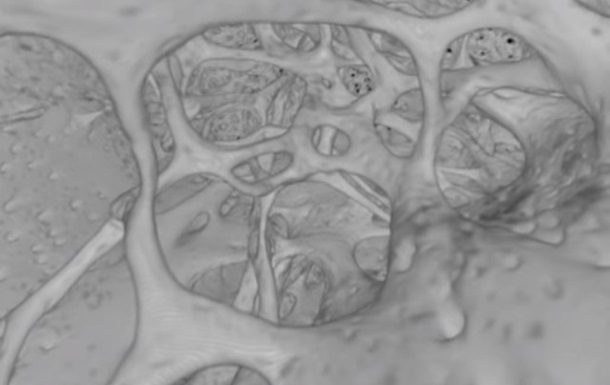

В ходе эксперимента ученые использовали химическое вещество этилциннамат на мышиных костях, чтобы сделать их прозрачными. После этого, используя световую флуоресцентную и рентгеновскую микроскопию, они сумели обнаружить несколько сотен капилляров, названных транскортикальными сосудами.

По словам исследователей, большая берцовая кость мыши может содержать более тысячи таких кровеносных сосудов, при этом через них проходит более 80% артериальной и 59% венозной крови.

В большой берцовой кости человека обнаружили похожую систему с более толстыми кровеносными сосудами. Однако, по признанию исследователей, для определения их точных функций требуются дальнейшие эксперименты.